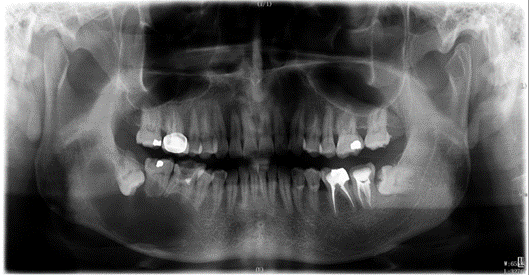

曲面断层全景片可发挥以下作用:

①判断整体牙齿情况、龋坏、残根或缺失情况;

②判断整体牙周情况、牙槽骨健康及吸收情况;

③判断阻生牙与周围牙体及结构,如下颌神经管的位置关系;

④判断颞下颌关节的对称度及形态情况;

⑤对上下颌骨、上颌窦、窦底轮廓等解剖的健康情况判断;

⑥对患者颌面部肿瘤、囊肿、畸形等的筛查和鉴别;

⑦对外伤患者上下颌骨、颧骨骨折形态、牙根情况的判断;

⑧对儿童乳恒牙牙胚、牙列等的发育情况判断;